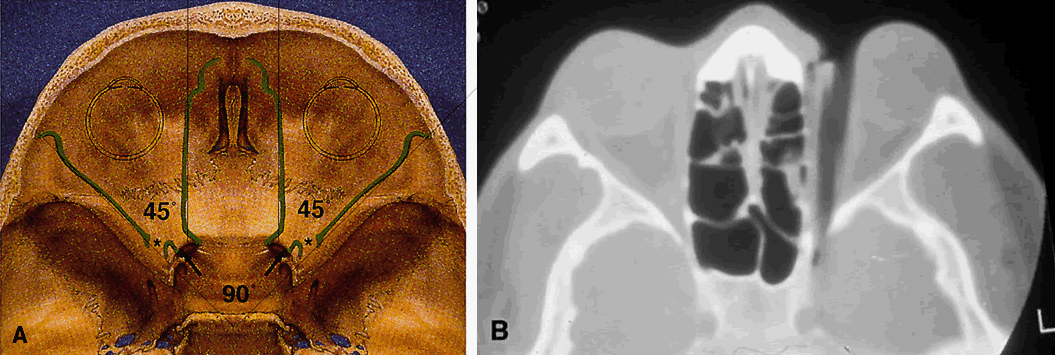

The lesser wing of the sphenoid bone is initially cartilaginous, but the greater wing and the rest of the orbital bones are membranous in nature and ossify and fuse between the 6th and 7th months of gestation. As the orbital bones develop, the eyes converge from an initial 180° relation to their final position of 68°, achieved in infancy. However, the orbital axis remains somewhat divergent at birth (115° between the lateral orbital wall and the skull axis) when compared with that of adults (45°) (Fig. 4).15

The SOF is 22 mm long and separates the greater and lesser wings of the sphenoid bone. Note in Figure 8 that it lies lateral and slightly below the optic foramen in radiographic studies. Also note that the (SOF, and not the optic foramen, is located at the apex of the orbit (Fig. 11). The SOF is split into two compartments by the lateral rectus muscle. The medial compartment contains the oculomotor (superior and inferior divisions) nerve, nasociliary nerve, abducens nerve, sympathetic and parasympathetic fibers, and superior ophthalmic vein. The lateral compartment transmits the lacrimal, frontal, and trochlear nerves. This extraconal location of the trochlear nerve is appreciated clinically after retrobulbar anesthesia. Although the anesthetic block effectively causes akinesia of the EOMs, the patient often can still intort the globe because of the intact innervation to the superior oblique muscle.

Fig. 11. Osteology. A. An axial view of the orbital roof demonstrates the parallel course of the medial orbital walls (green). The lateral orbital walls (green) lie at an angle of 90° from each other, or 45° from each medial wall. Remember that the superior orbital fissure, and not the medially placed optic canal, lies at the posterior aspect of the orbit. B. CT of a wooden foreign body within the orbit after trauma. Note that the tip has traveled through the superior orbital fissure and lies within the CS, not the optic canal. In this case, the greatest worry was not the patient's vision, but the possibility of lacerating injury of the carotid siphon, which was confirmed on subsequent arteriography (A modified from Zide BM, Jelks GW: Surgical Anatomy of the Orbit, p 9. New York, Raven Press, 1985. B courtesy John W. Shore, MD, Austin, TX)